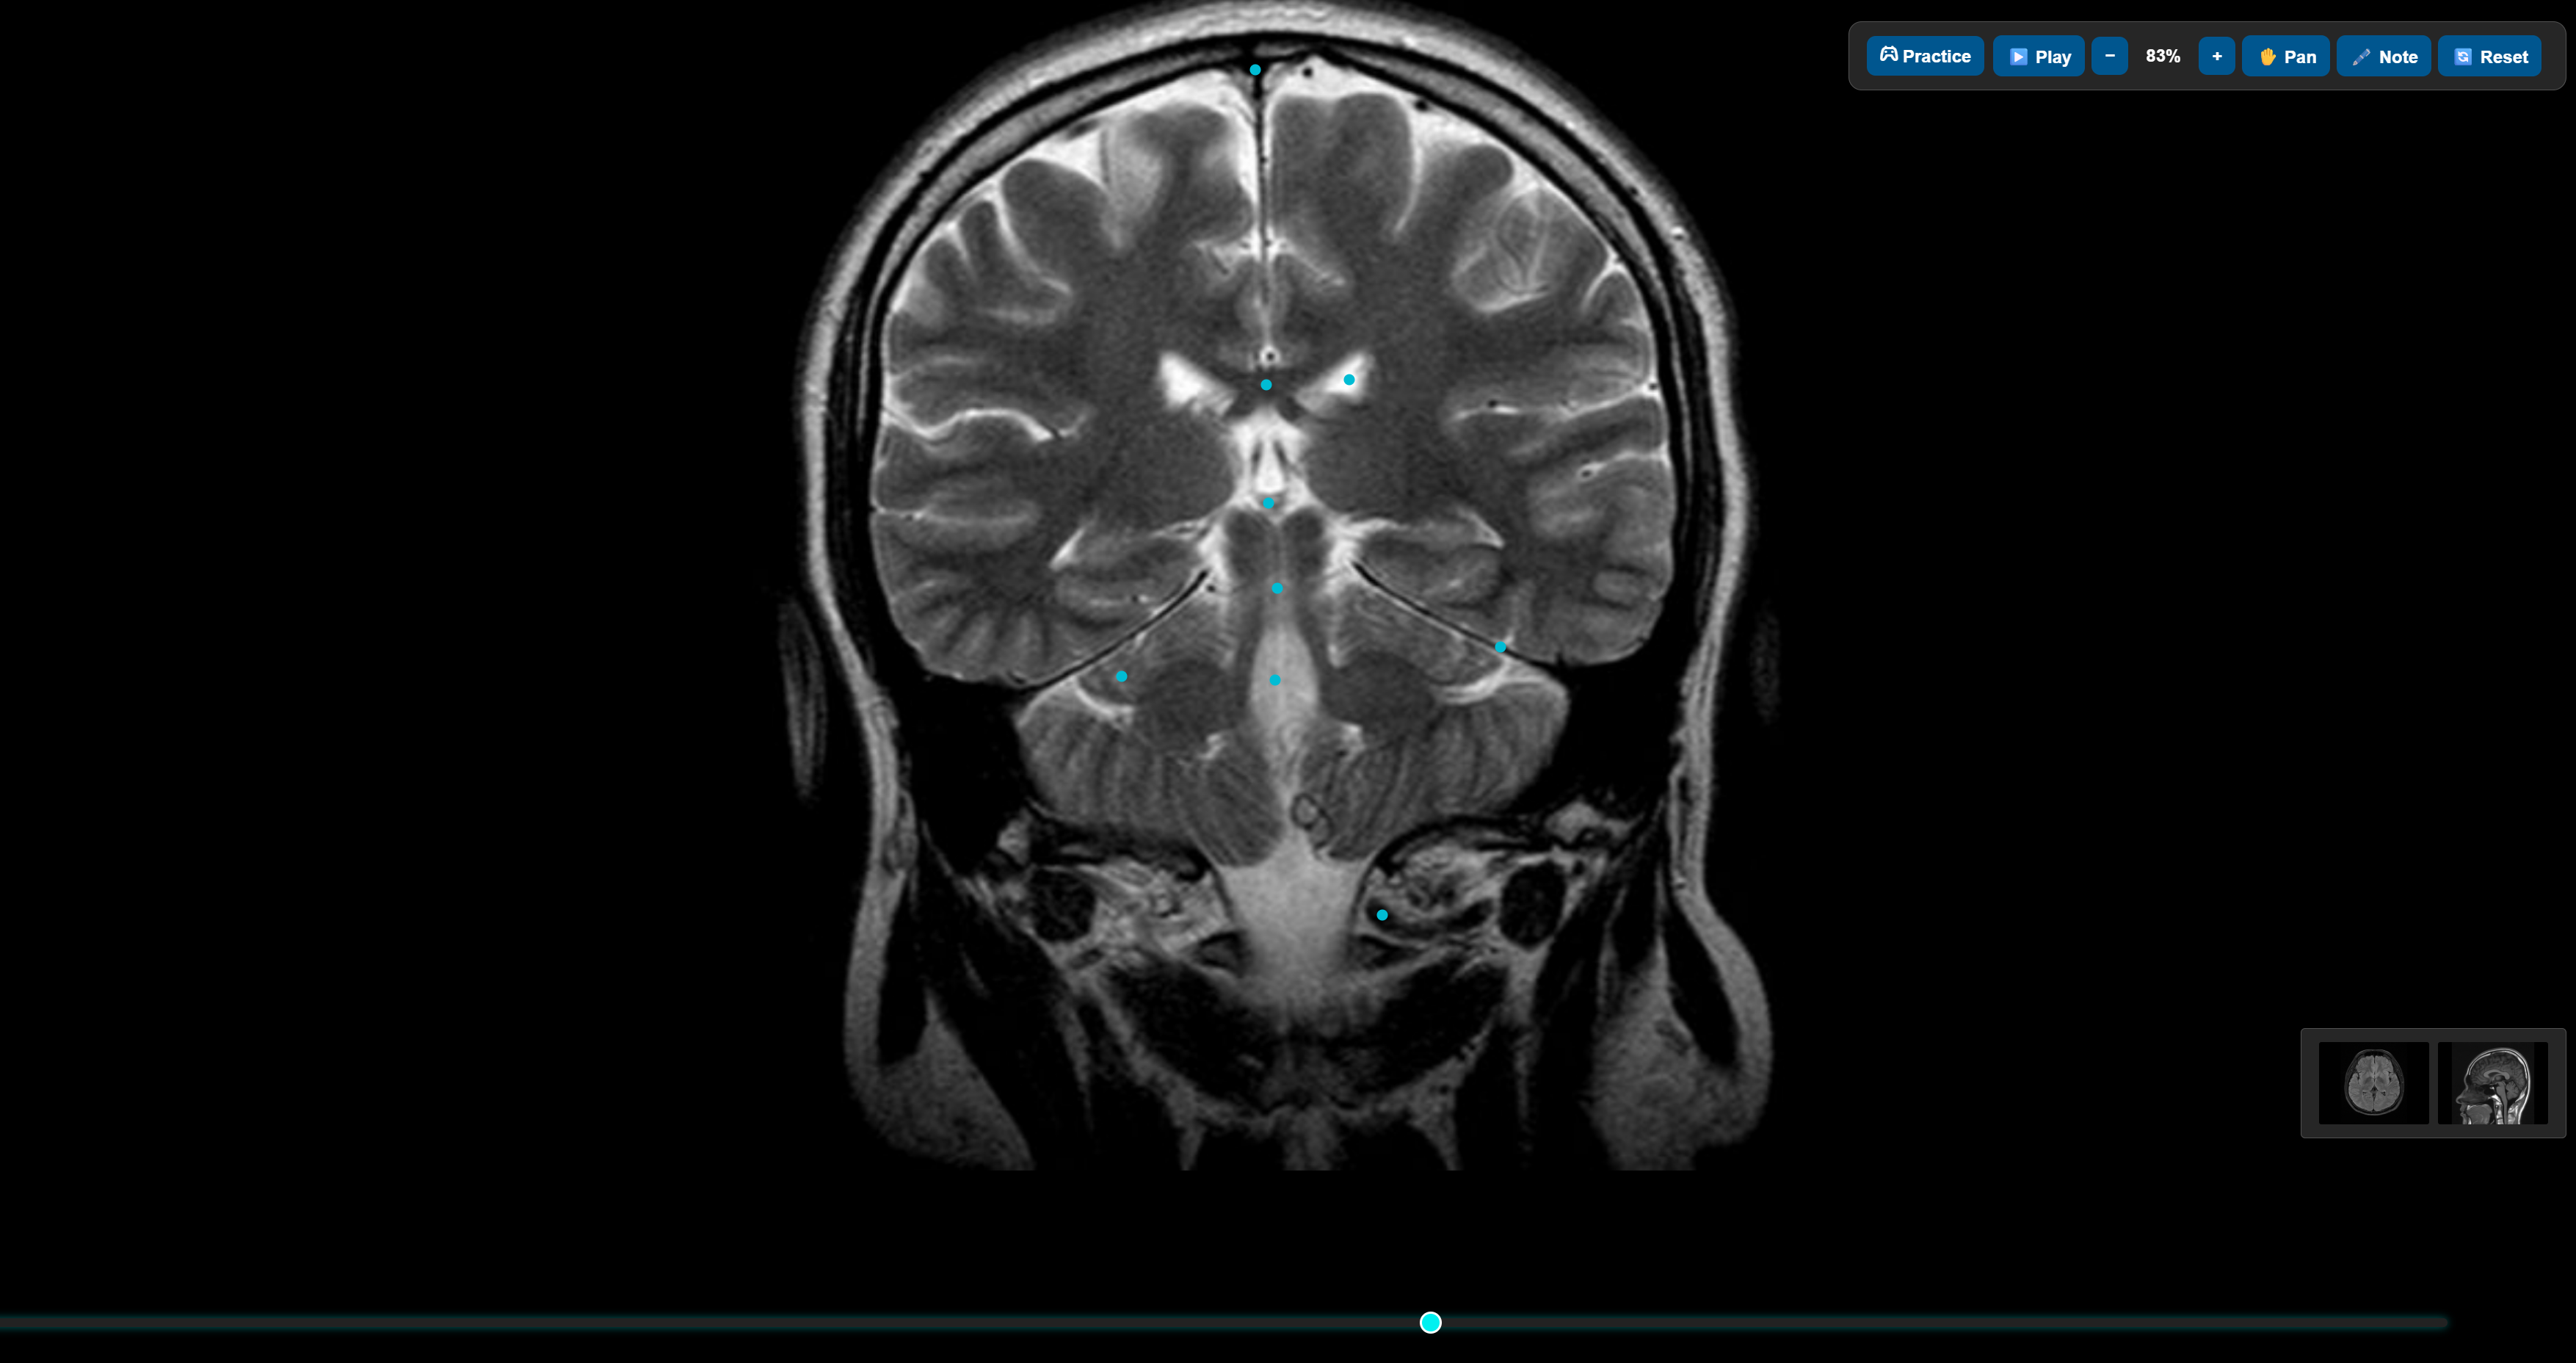

Image Matching

Practice with a growing library of real-world image matching cases and get feedback in real time. Line up anatomy, nudge the couch, and get instant feedback on whether you’re within training tolerances.

CT anatomy practice X-ray anatomy practice MRI anatomy practice

Medical Imaging

Practise anatomy directly on CT scans, X-rays, and MRI.

• Labelled cross-sectional anatomy on CT, X-ray, and MRI.

• Perfect for building confidence before clinical placement.